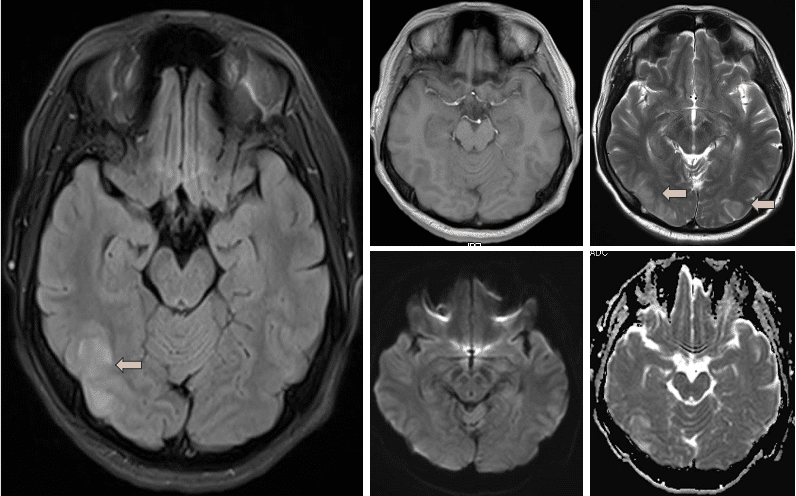

头MR(2023-11-08)左一为Flair序列,右四图自左向右、由上而下依次为T1、T2、DWI及ADC序列,双侧顶枕叶脑皮质可见稍长T1WI、T2WI信号,Flair呈高信号影,增强未见异常强化影。

Ps:癫痫发作部分人群在神经影像上可出现皮层信号异常,往往提示局部水肿形成,数日后可逐渐消退。影像学上容易于脑梗死患者混淆,注意结合病史鉴别。